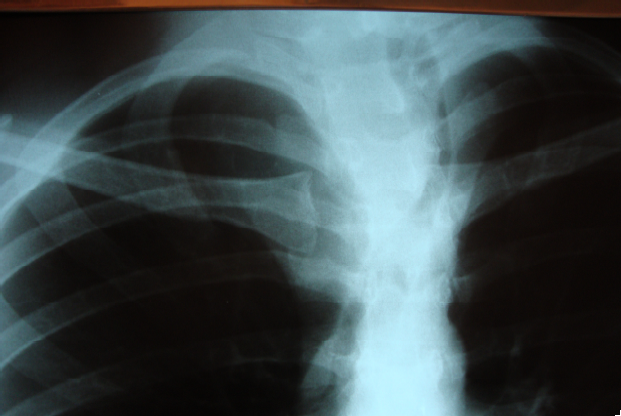

Devido ao crescimento rápido de lesão cervical que, atualmente, apresenta o tamanho de 10 cm x 6 cm, associada à perda ponderal de seis kg, nos últimos quatro meses, um homem de 30 anos de idade procurou o ambulatório de cirurgia geral. Relata nódulo tireoidiano, descoberto há quatro anos, em lobo direito, que era assintomático. Realizou punção biópsia com agulha fina guiada por US que revelou tumor folicular. No momento, a dosagem hormonal é normal e nega sintomas compressivos. O paciente realizou radiografia de tórax que pode ser visualizada abaixo.